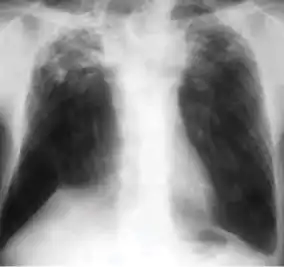

1. Infiltrate or consolidation - Opacification of airspaces within the lung parenchyma. Consolidation or infiltrate can be dense or patchy and might have irregular, ill-defined, or hazy borders.

Dense homogenous opacity in right, middle and lower lobe of primary pulmonary TB.